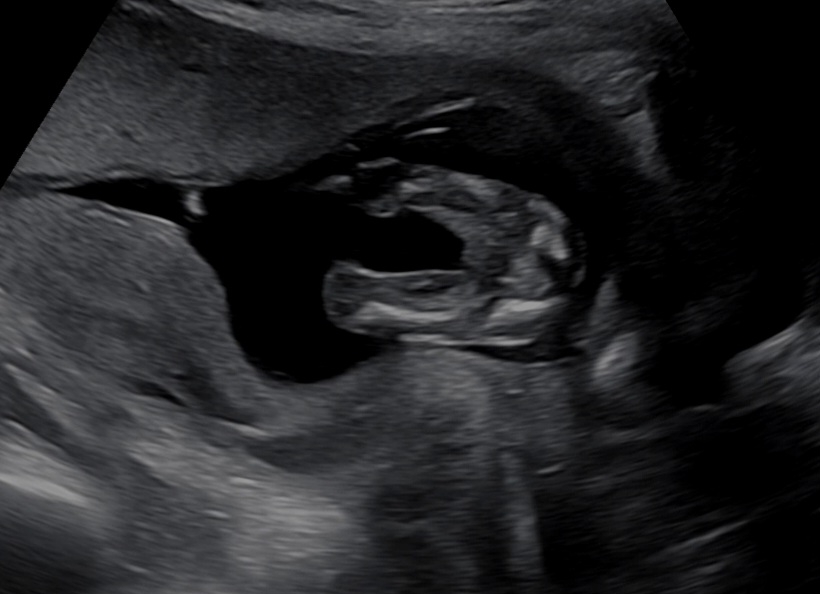

성별 궁금해요

오늘 딱 15주 되는 날인데 다리를 베베 꼬다가 겨우 보여주더라구요 의사선생님이 딸인거같다고 하셨는데 혹시나 나중에 갔는데 고추가 뿅 있는건 아니겠죠..?ㅎㅎㅎ